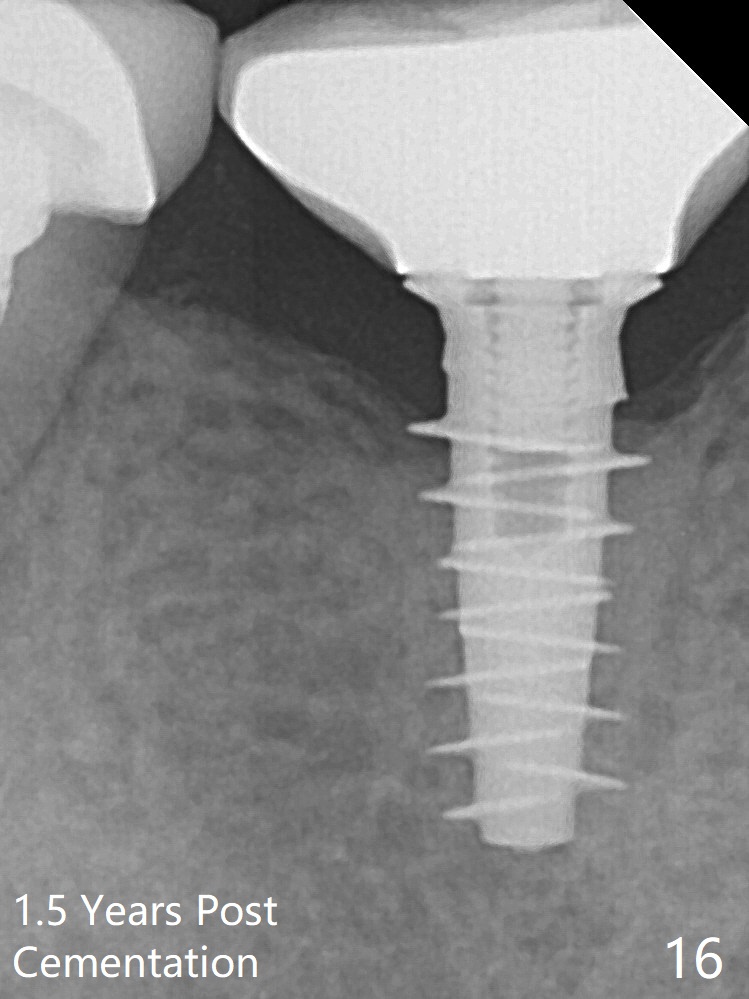

The bone density immediately around the implant appears to increase 1.5 years post cementation (Fig.15,16).